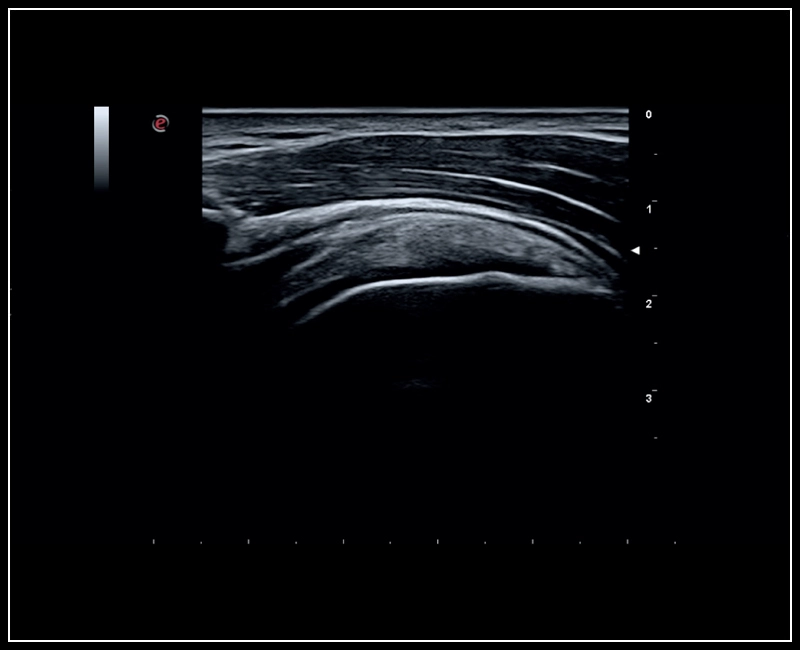

MyLab™Sigma - MSK imaging of the shoulder

MyLab™Sigma - MSK imaging of the shoulder